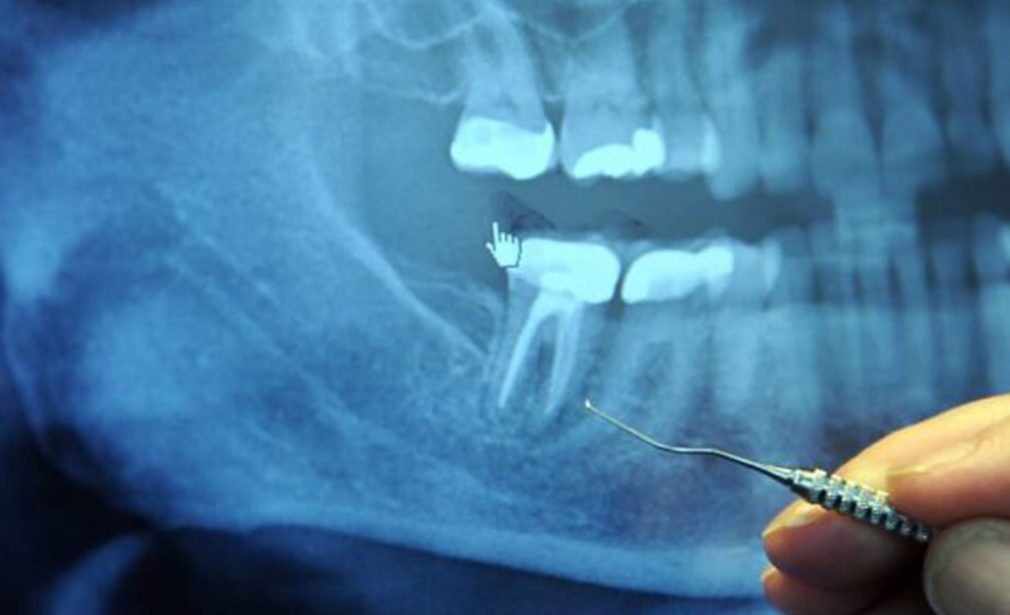

Root Canal in Miami begins with a detailed dental examination and digital imaging. This allows our dentist to identify the exact source of infection and evaluate the surrounding tooth structure.

During the procedure, the dentist carefully removes the infected pulp from the inside of the tooth. The root canals are then cleaned, disinfected, and shaped using precise instruments designed to maintain comfort and accuracy.